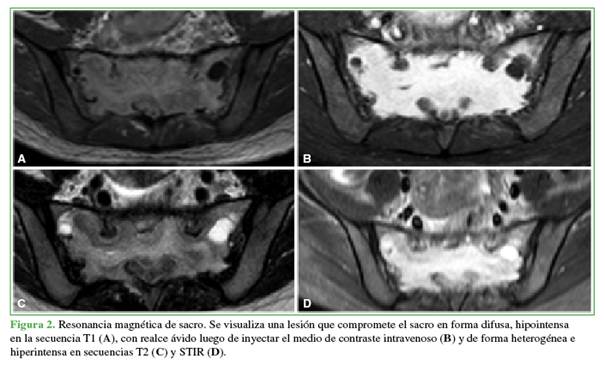

La resonancia magnética reveló una lesión que comprometía el sacro de forma difusa, hipointensa en la secuencia T1 (Figura 2A), con realce ávido luego de inyectar el medio de contraste intravenoso (Figura 2B) y de forma heterogénea e hiperintensa en las secuencias T2 y STIR (Figura 2C y D).